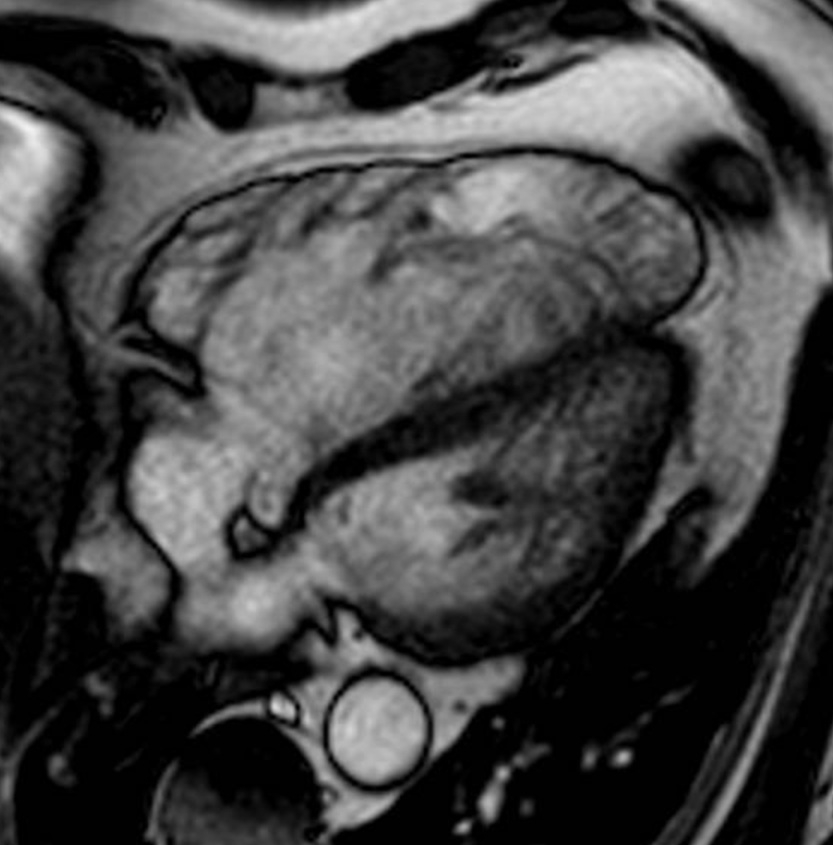

A 57-year-old male, hypertensive and former smoker, with a history of native PV IE in 2015 (no predisposing factors), treated with antibiotics and good clinical outcome, presented in May 2024 with NYHA class II dyspnea and lower limb edema. Echocardiography showed right ventricular (RV) dilation (basal: 61 mm; mid: 58 mm), TAPSE 29 mm, thickened and partially calcified PV with severe regurgitation (PHT 90 ms; diastolic reflux in branches), and no pulmonary hypertension. Cardiac MRI confirmed severe RV dilation (EDV: 387 ml; iEDV: 150 ml/m2) (Image 1), RV ejection fraction 30%, severe pulmonary regurgitation (regurgitant fraction 63%), and dilation of the pulmonary artery trunk and branches. Given symptomatic severe RV dysfunction and high surgical risk, a percutaneous approach was selected. Cardiac CT revealed a dilated RVOT (minimum diameter 35.4 x 37.7 mm; area 10.5 cm2), trunk (43.8 x 45.5 mm; area 15.1 cm2), right branch (28.6 x 29.7 mm; area 6.67 cm2), and left branch (27.6 x 30.2 mm; area 6.55 cm2). Due to unsuitable anatomy for RVOT or main trunk valve placement, two Myval N 32 valves were implanted percutaneously in each pulmonary artery branch (Image 2). The procedure was successful and uneventful. The patient improved clinically; follow-up echocardiogram showed well-functioning prostheses, minimal paravalvular regurgitation, and reduced RV dimensions (basal: 56 mm; mid: 47 mm).